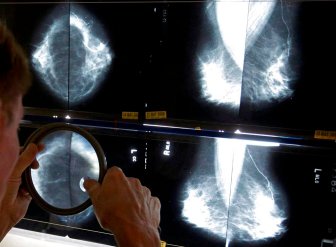

Mammograms

Alberta lowers age for women to be screened for breast cancerAlberta Health Services has lowered the recommended age for biennial breast cancer screening for average-risk women from 50 to 45.HealthOct 18, 2022

Cancer foundations in Saskatchewan launch fundraiser to save the ‘Breast Screening Bus’Since 2002, the Breast Screening Bus provided mammograms for residents in rural and remote communities of Saskatchewan, but funding is now needed for a new bus.HealthOct 3, 2022

15 patients in N.L. require followup as review of thousands of mammograms continuesThe province's health authorities have identified 15 patients this week requiring further followup as a review continues of thousands of mammograms.HealthSep 15, 2022

‘How the hell did this happen?’ More than 16,500 mammograms under review across N.L.Officials from three of the province's four health authorities told reporters the approximately 13,884 mammograms under scrutiny represent about 11,751 patients.HealthAug 31, 2022

Newfoundland health authority reviewing about 3,000 mammograms for possible issuesThe health authority will review its mammogram viewing procedures and look at whether this error occurred because staff had been working from home during the COVID-19 pandemic.HealthAug 24, 2022

Disabled women in Quebec still struggling with mammogram access: advocatesA community group advocating for people with disabilities claims some women are having trouble getting access to mammograms.CanadaMay 4, 2022

AI can spot breast cancer better than humans, study findsArtificial intelligence programs are better at spotting cancer than humans, a new study suggests. What does that mean for cancer detection?HealthJan 1, 2020

Many women aren’t told they have dense breasts. Here’s why it matters43 per cent of women ages 40 to 74 have dense breasts, and they can have serious implications.LifestyleOct 3, 2019

New breast cancer screening guidelines are outdated and dangerous, experts sayMore than 130 breast-cancer doctors and researchers disagree with new screening recommendations, saying the task force is basing their recommendations on outdated data.HealthJan 28, 2019

Patients should decide when to get mammograms: Canadian health expertsNew guidelines from the Canadian task force on preventive health are empowering women to take charge of their health when it comes to breast cancer screening.HealthDec 10, 2018